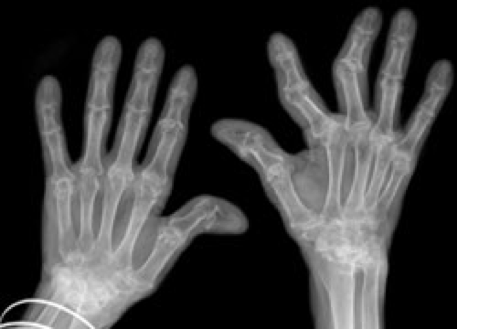

-Inflammation of one or more of your joints

-Includes more than 100 different rheumatic diseases